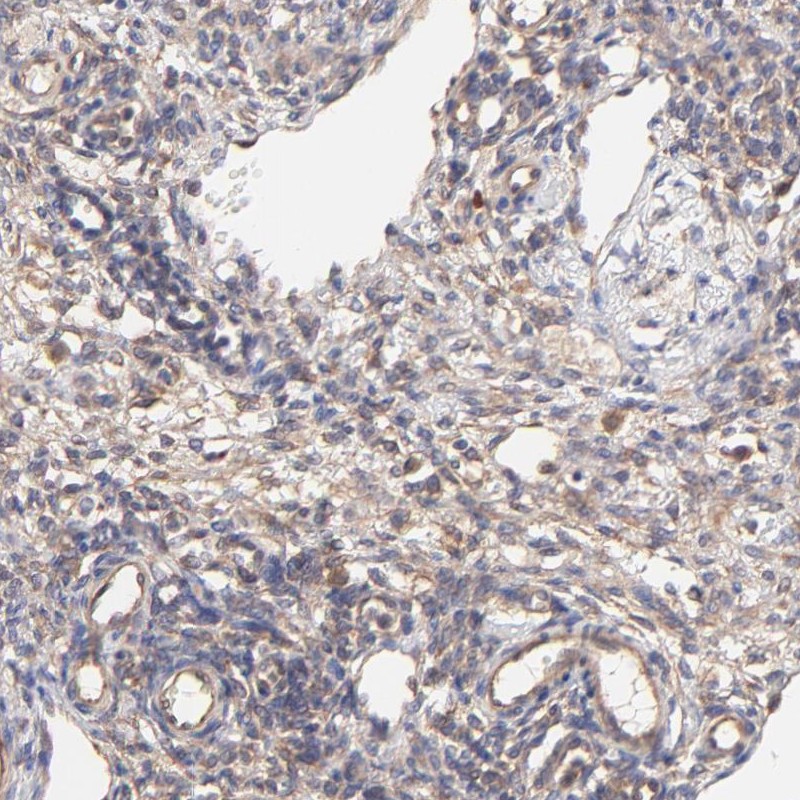

Immunohistochemical staining of human ovary shows moderate cytoplasmic positivity in ovarian stroma cells.